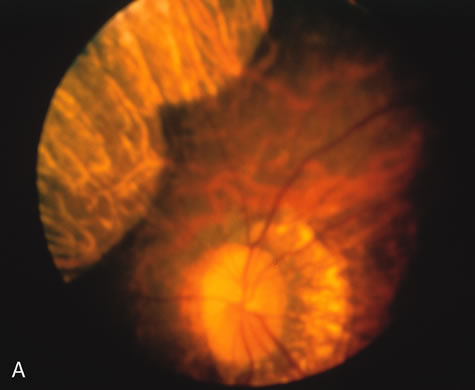

In retinitis pigmentosa (RP), the pigment abnormalities of atrophy, migration, and clumping are made apparent by transmitted hyperfluorescence and blocked hypofluorescence (Fig. 1A). Patients who have very minimal pigmentary alterations (pauci pigmentary RP) or no pigment abnormalities (RP sine pigmento) may show the abnormalities on fluorescien angiography (FA). It is uncommon to see choriocapillaris atrophy except in the late stages. This finding corresponds to the histopathology, which shows that the earliest abnormalities are in the photoreceptors and that the choroid is normal.1

Fig. 1. Retinitis pigmentosa. A. A typical area of bone spicule pigmentation. B. Diffuse dye leakage is apparent throughout the posterior pole. C. The early angiogram shows dilated and irregular retinal radial peripapillary capillaries and perifoveal retinal capillaries. D. Leakage from these vessels are evident in the late angiogram.

Dye leakage in RP may occur from the retinal vessels or at the level of the retinal pigment epithelium (Fig. 1B).2–4 The leakage may be seen in the macula and posterior pole, along the vascular arcades in the distribution of the radial peripapillary capillaries, and in the periphery (where an exudative vasculopathy resembling Coats' disease is suggested).

Of more clinical importance is the role of FA in the diagnosis and treatment of cystoid macular edema (CME) (Fig. 1C and D). Stereoscopic FA indicates that the leakage, which may be diffuse or have the typical petaloid stellate appearance of CME, can come from the perifoveal retinal capillaries, from the choroid through the RPE, or from a combination of both sources.4 With the recent suggestion that CME in RP may be successfully treated with acetazolamide,5, 6 FA is thus important to document the diagnosis of CME, establish the origin(s) of leakage, and follow patients during and after therapy.